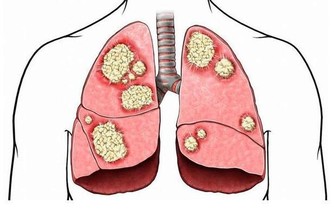

俗話說“傷在兒身,痛在娘心”,有時候孩子生病更令大人傷心,恨不得所有的痛苦由自己代替。今天要說的是白血病,聽到這個病相信很多人第一印象就是光著頭、戴著口罩的孩子,他們不能隨便外出,不能亂吃外面的餐飲,擔心交叉感染。看著孩子眼巴巴地望著窗外同齡小伙伴自由奔跑,大人心裡也不好受。

為什麼總有孩子得白血病?白血病和家裡的環境有關嗎?

在兒童腫瘤數據中,超過一半的數據由白血病“貢獻”,而且還在以每年3-4萬的速度往上增加。在治療的同時我們也在深思,為什麼受傷的總是孩子?

孩子身體有效,但是細胞很活躍,代謝和更新的速度比成年人快,如果外界環境中存在不良因素,細胞在分裂的過程中就可能“出差錯”,最後形成癌細胞。